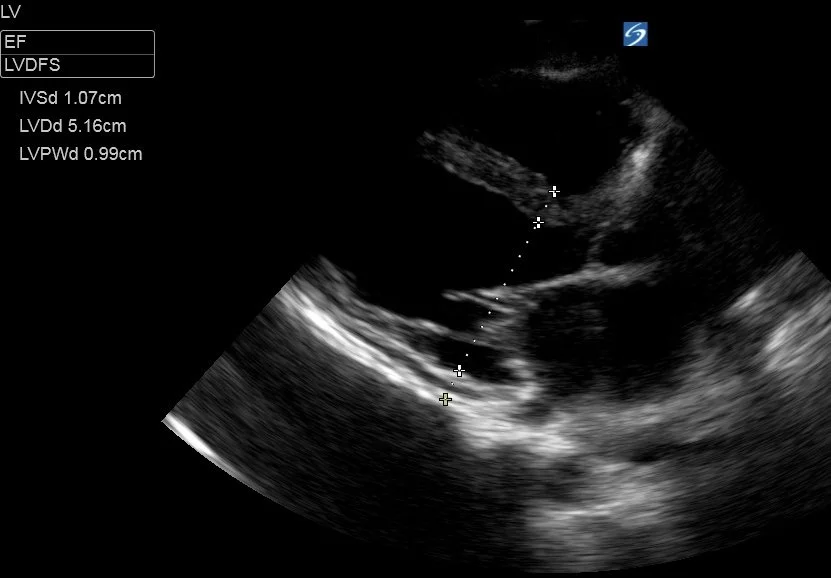

Fractional Shortening (FS):

This method measures the size of the LV base at end-diastole and end-systole, using the difference to calculate the ‘shortening’ of the LV basal diameter. FS is the difference (diastole - systole), divided by the diastolic diameter (x100 to give a %). A normal fractional shortening is around 25-45%. This can be converted to an EF using the ‘Teichholz’ method which assumes the LV is a hollow cone with a uniformly ‘shortening’ diameter (not a perfect model) and the machine will calculate this for you.

To measure the LV base you must obtain a good PLAX view and freeze the clip, before cycling through the frames to find end-diastole (called LVDd aka LVEDD - immediately as the mitral valve closes, when the LV cavity is at its largest), and measuring the LV base through a line through the tips of the mitral valve. Do the same for end-systole (LVDs aka LVESD - the frame immediately before the MV opens, when the LV cavity is at it’s smallest), this time measuring fractionally further towards the apex to allow for the systolic excursion of the mitral valve.

Tips:

• measure perpendicularly across the LV [inner edge to inner edge of the myocardium] . The benefit of this method over M-mode is that you can measure more vertically-orientated hearts in which it is often impossible to get the M-mode cursor to track across the LV base faithfully.

• watch several cardiac cycles to get an idea of where the LV walls reach during systole to make an accurate measurement of LVDs

• This method also gives you an objective LV size, and allows diagnosis of LV dilation (a normal LVDd is generally < 5.5cm but there are differing ranges for men and women, and it is usually indexed to BSA)

This patient had a LVDd of 5.16cm and LVDs of 4.63cm

Fractional Shortening was ((5.16-4.63)/5.16) x 100 = 10%.

This is severe LV impairment.